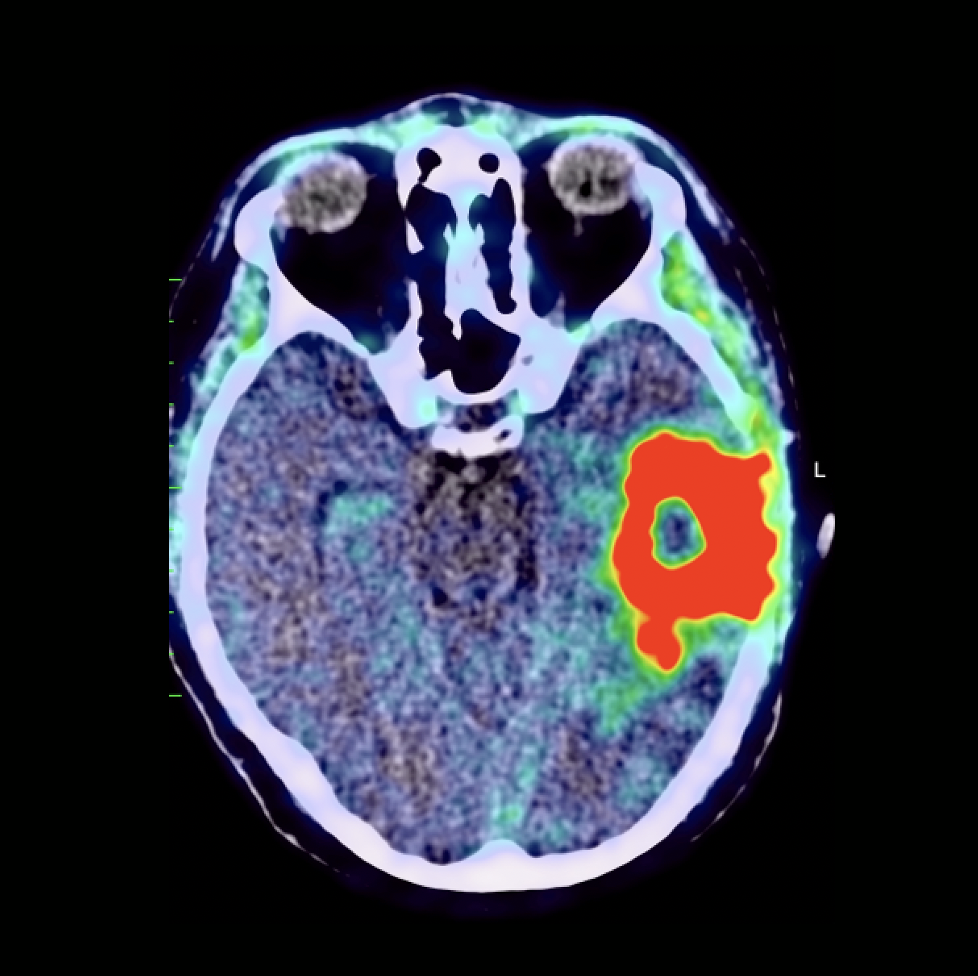

Current Oncology Free FullText Surgical Management of Brain Tumors